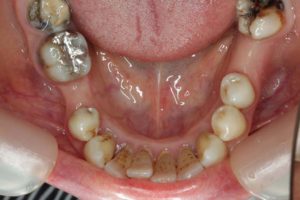

どのように変わったか、下の写真をご覧ください。

長い間お疲れ様でした。この患者さんは、奥歯を何本も失っていて満足なお食事ができない状態でした。前歯も所々虫歯で黒ずんでいて気になって口を開けて笑えないとおっしゃっていました。そもそも、最初はお嬢様の結婚の前までに綺麗にしたいというものだったのですが、治療をしていくうちに奥歯の大切さを実感していただいたようです。

奥歯にインプラントを入れ、前歯はホワイトニングやダイレクトボンディング、セラミックなどで修復しました。